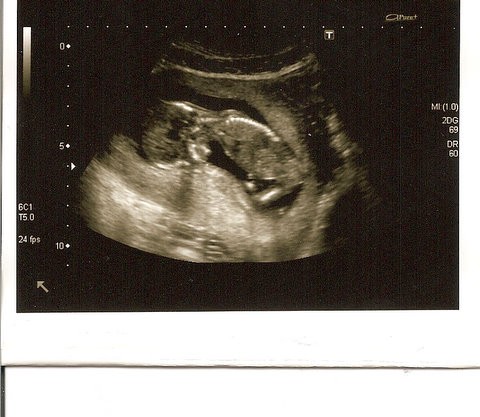

A to moja malutka istotka :-) leży sobie na brzuszku. Z lewej strony widać nóżki a z prawej główka. Zdjęcie zostało zrobione w 12tc4d i wtedy miał od czubka puki do główki 6,91cm :-)

• 12tc4d.JPG

12tc4d.JPG

60,8 KB · Wyświetleń: 121